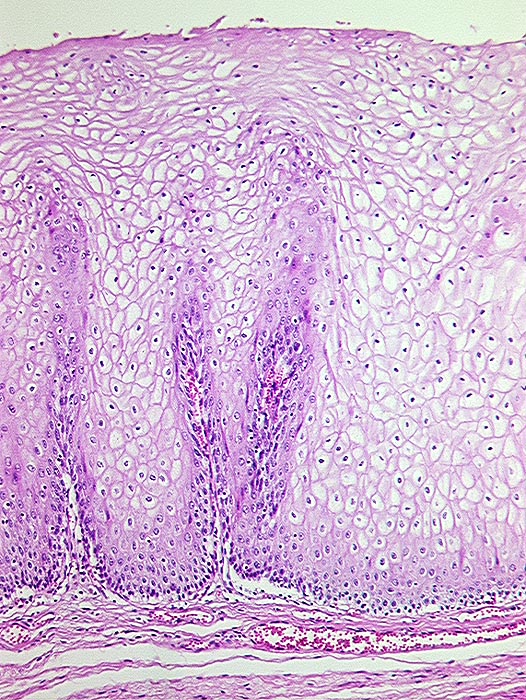

• Präneoplastisch veränderte Mukosa im Randbereich des Karzinoms mit ausgeprägten Zellatypien in der gesamten Epithelbreite und zahlreichen Mitosen (Carcinoma in situ).

Mikroskopisch zeigen die meisten Plattenepithelkarzinome einen mittleren Differenzierungsgrad und eine wechselnd starke Verhornung. Das fortgeschrittene Karzinom infiltriert angrenzende Strukturen wie den Tracheobronchialbaum, die Aorta und den Nervus recurrens.

• Der Tumor bildet anastomosierende solide Zellstränge, die fokal im Zentrum verhornen.

• Tumorzellen mit reichlich glasigem eosinophilem Zytoplasma und scharfen Zellgrenzen mit stachelförmigen Interzellularbrücken. Stark vergrösserte, pleomorphe, hyperchromatische Zellkerne mit prominenten Nukleolen.